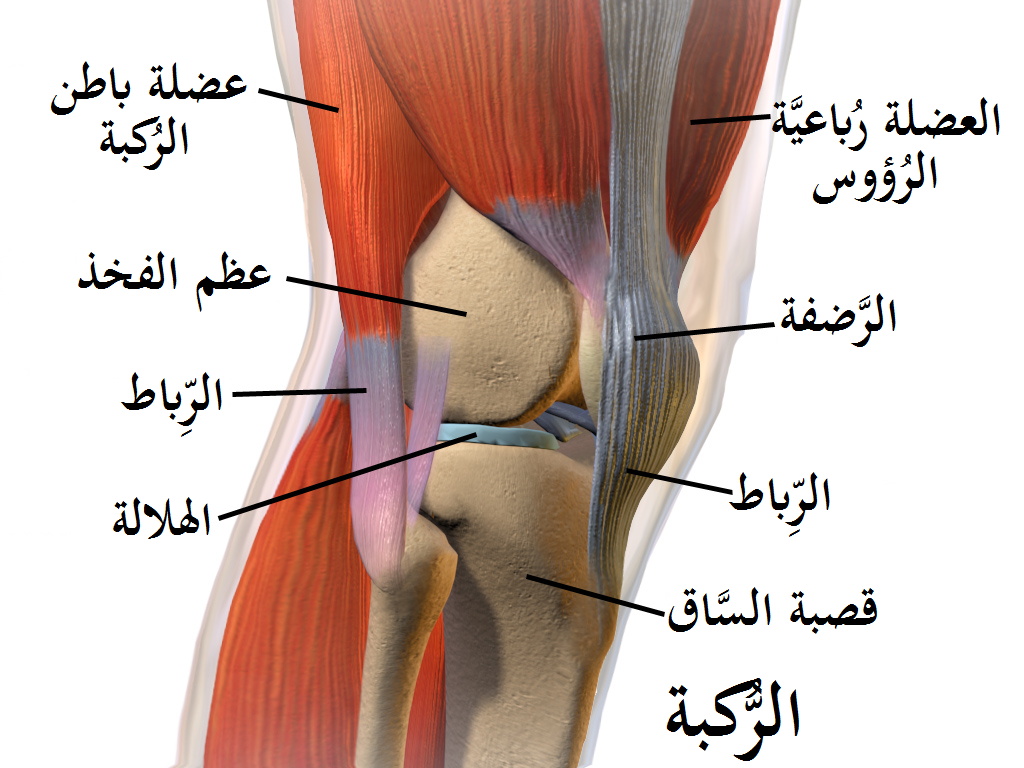

العظام

حيث يوجد في الركبة ثلاث أجزاء من العظام وهم:

- عظم الفخذ: ويسمى عظام الفخذ العلوي وتتصل في نهايتها بعظم الساق.

- عظام الساق: وهو عظام الساق السفلي وتسمى (الظنبوب).

- الرضفة: ويطلق عليها صابونة الركبة وتوجد أمام المفصل وفوق عظم الفخذ.

الأربطة

يوجد نوعان من الأربطة وهما:

- الرباط الصليبي الأمامي والخلفي: حيث تساعد في حركة الركبة والمحافظة على استقرارها.

- الأربطة الجانبية: حيث توجد على جانبي الركبة وتعمل على تثبيتها وهما ( الإنسية والجانبية).

الغضاريف

- الغضاريف الهلالية: يكونان على شكل هلال، وتتمثل وظيفتهما في امتصاص الصدمات التي يتعرض إليها الشخص، كما أنها تعمل على تحسين توافق العظام.

- الغضروف الزجاجي: حيث يعمل هذا الغضروف على تقليل الاحتكاك وتسهيل الحركة أيضًا ويوجد في نهاية العظام.

الأوتار والسائل الزلالي

الأوتار عبارة عن هياكل تقوم بالربط بين العضلات القوية مثل ( عضلات الفخذ الرباعية وأوتار الركبة) التي توجد حول الركبة كما تساعد بشكل كبير في حركة الركبة بصفة عامة، أما بالنسبة للسائل الزلالي فهو يكون بين الغضاريف من أجل تقليل الاحتكاك كما أنه يساعد في اليونة و الحركة نفسها.